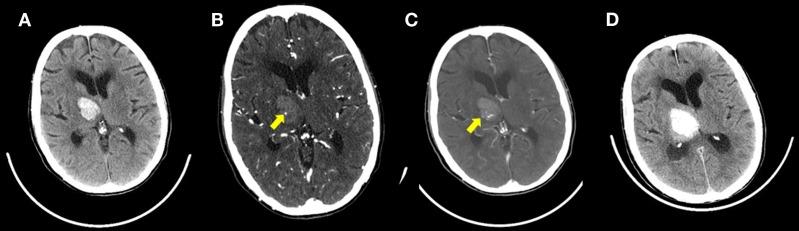

Despite improvements in management and prevention of intracerebral hemorrhage (ICH), there has been little improvement in mortality over the last 30 years. Hematoma expansion, primarily during the first few hours is highly predictive of neurological deterioration, poor functional outcome, and mortality. For each 10% increase in ICH size, there is a 5% increase in mortality and an additional 16% chance of poorer functional outcome. As such, both the identification and prevention of hematoma expansion are attractive therapeutic targets in ICH. Previous studies suggest that contrast extravasation seen on CT Angiography (CTA), MRI, and digital subtraction angiography correlates with hematoma growth, indicating ongoing bleeding. Contrast extravasation on the arterial phase of a CTA has been coined the CTA Spot Sign. These easily identifiable foci of contrast enhancement have been identified as independent predictors of hematoma growth, mortality, and clinical outcome in primary ICH. The Spot Sign score, developed to stratify risk of hematoma expansion, has shown high inter-observer agreement. Post-contrast leakage or delayed CTA Spot Sign, on post contrast CT following CTA or delayed CTA respectively are seen in an additional ∼8% of patients and explain apparently false negative observations on early CTA imaging in patients subsequently undergoing hematoma expansion. CT perfusion provides an opportunity to acquire dynamic imaging and has been shown to quantify rates of contrast extravasation. Intravenous recombinant factor VIIa (rFVIIa) within 4 h of ICH onset has been shown to significantly reduce hematoma growth. However, clinical efficacy has yet to be proven. There is compelling evidence that cerebral amyloid angiopathy (CAA) may precede the radiographic evidence of vascular disease and as such contribute to microbleeding. The interplay between microbleeding, CAA, CTA Spot Sign and genetic composition (ApoE genotype) may be crucial in developing a risk model for ICH.

尽管在脑出血(ICH)的管理和预防方面有所改进,但在过去30年中死亡率几乎没有改善。血肿扩大,主要是在最初几个小时内,是神经功能恶化、功能预后不良和死亡率的高度预测指标。脑出血体积每增加10%,死亡率就增加5%,功能预后较差的可能性增加16%。因此,识别和预防血肿扩大都是脑出血有吸引力的治疗靶点。先前的研究表明,在CT血管造影(CTA)、MRI和数字减影血管造影上看到的造影剂外渗与血肿生长相关,表明存在持续出血。CTA动脉期的造影剂外渗被称为CTA斑点征。这些易于识别的造影剂强化灶已被确定为原发性脑出血血肿生长、死亡率和临床结局的独立预测指标。为分层血肿扩大风险而制定的斑点征评分显示观察者间一致性较高。在CTA后对比增强CT或延迟CTA上分别出现的对比剂渗漏或延迟CTA斑点征,在另外约8%的患者中可见,这解释了随后发生血肿扩大的患者早期CTA成像上明显的假阴性观察结果。CT灌注提供了获取动态成像的机会,并已被证明可以量化造影剂外渗率。脑出血发病后4小时内静脉注射重组凝血因子VIIa(rFVIIa)已被证明可显著减少血肿生长。然而,临床疗效尚未得到证实。有令人信服的证据表明,脑淀粉样血管病(CAA)可能先于血管疾病的影像学证据出现,因此导致微出血。微出血、CAA、CTA斑点征和基因组成(载脂蛋白E基因型)之间的相互作用可能对建立脑出血风险模型至关重要。